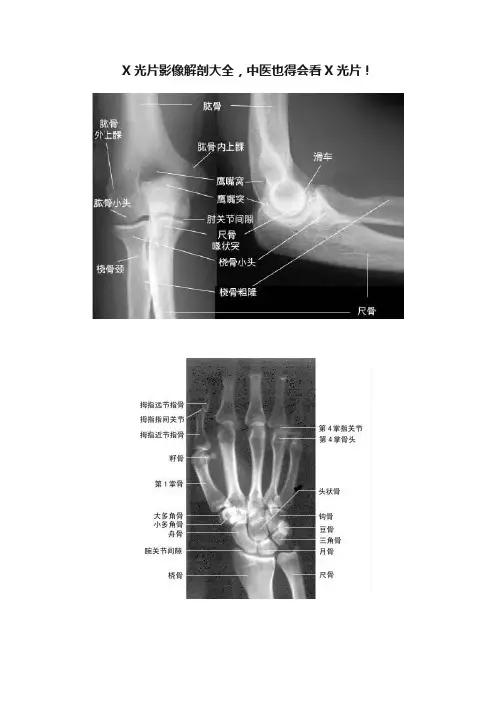

X光片影像解剖大全,中医也得会看X光片!胸部X线片系统读片原理24个字母(A-X)系统读片法,可以减少漏诊。